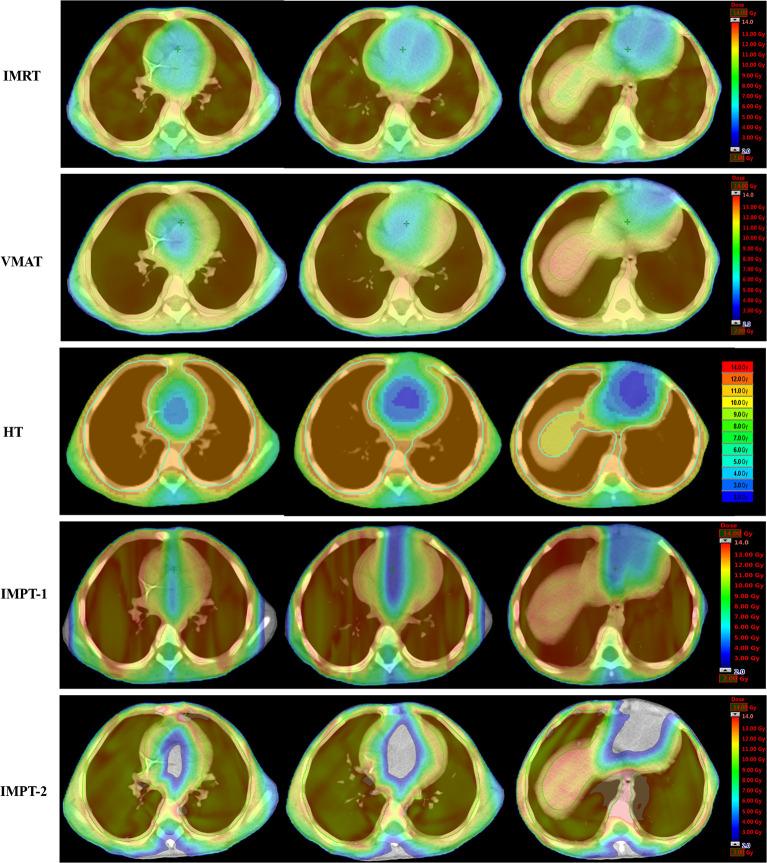

METHODS

Eleven patients with pediatric tumors and pulmonary metastasis treated with 12 Gy WLI (all received volumetric-modulated arc therapy (VMAT)) in our institute between 2010 and 2019 were retrospectively selected. Each patient was replanned with intensity-modulated radiation therapy (IMRT), helical tomotherapy (HT), and two intensity-modulated proton radiotherapy (IMPT) plans (IMPT-1 and IMPT-2). IMPT-1 considered the whole lung as the planning target volume (PTV), utilizing the anteroposterior technique (0/180°). IMPT-2 was a new proton solution that we proposed in this research. This approach considered the unilateral lung as the PTV, and 3 ipsilateral fields were designed for each lung. Then, IMPT-2 was generated by summing two unilateral lung plans. The primary objective was to obtain adequate coverage (95% of the prescription dose to the PTV) while maximally sparing the dose to the heart. The PTV coverage, conformity index (CI), homogeneity index (HI), and dose-volume statistics of the heart and substructures were assessed by means of the averages of each comparison parameter.

All treatment techniques achieved the target volume coverage required by clinical practice. HT yielded the best coverage and homogeneity for the target structure compared with other techniques. The CI from IMRT was excellent. For photon radiation therapy, the HT plan afforded superior dose sparing for the V, V, V, V, and D of the heart and D of the right ventricle (RV). IMRT displayed the most notable dose reductions in the V, V, V, and V of the heart and D of the right atrium (RA). The VMAT plan was the least effective on the heart and substructures. However, compared with photon radiation therapy, IMPT-1 did not show an advantage for heart protection. Interestingly, IMPT-2 provided significant superiority in cardiac sparing, including maximum dose sparing for the V, V, V, V, V and D of the heart and D of the RA, RV, left atrium (LA) and left ventricle (LV) compared to all other techniques.